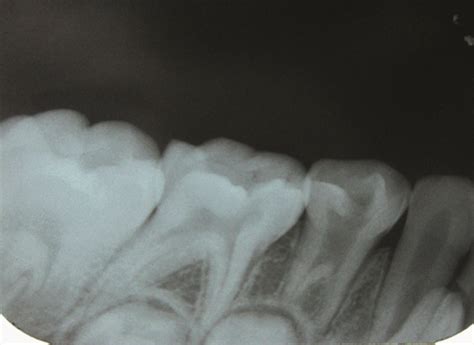

Root Amputation/Root Resection: An Efficient, Effective Means To Save A Multirooted Tooth

Root Resection – A Dark Horse in Management Offurcation Involved